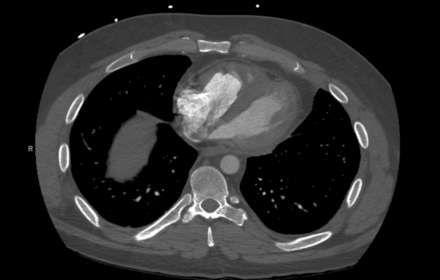

A middle-aged man with a history of asthma and chronic sinusitis presented with pleuritic chest pain, breathlessness, and numbness in his left arm. On examination, he was hypertensive, tachypneic, and hypoxic. Laboratory workup showed leukocytosis with marked eosinophilia (13.09 x 10^3/μL), elevated cardiac biomarkers, and proteinuria. Computed tomography angiography revealed subsegmental pulmonary embolism. Echocardiography showed a moderately dilated right ventricle with reduced systolic function. Cardiac imaging identified diffuse myocardial edema, subendocardial enhancement in the right ventricle, and an apical thrombus. Cerebral magnetic resonance imaging revealed multifocal diffusion-restricted lesions. Coronary angiography showed no obstructive disease. Given the constellation of asthma, eosinophilia, neuropathy, and sinus disease, eosinophilic granulomatosis with polyangiitis (EGPA) was strongly considered. Testing for clonal eosinophilic syndromes and antineutrophil cytoplasmic antibodies was negative. Immunosuppressive therapy, including Rituximab and Mepolizumab, was initiated. Follow-up imaging at 9 months demonstrated complete resolution of myocardial inflammation and thrombus.

Cardiac involvement in eosinophilic granulomatosis with polyangiitis is a major determinant of morbidity and mortality, contributing to nearly half of EGPA-related deaths. Clinical manifestations may include myocarditis, pericarditis, heart failure, or intracardiac thrombus. However, cardiac EGPA often lacks classic ischemic findings, making diagnosis challenging. Cardiac magnetic resonance imaging is the most sensitive modality for detecting myocardial inflammation, subendocardial fibrosis, and mural thrombus, particularly when endomyocardial biopsy is contraindicated. In this case, cardiac magnetic resonance imaging provided critical diagnostic clarity, revealing diffuse myocardial edema and subendocardial enhancement, features consistent with eosinophilic myocarditis. Integration of imaging findings with peripheral eosinophilia, asthma, neuropathy, and sinus disease enabled the timely recognition of EGPA. This case underscores the importance of early, multimodal cardiac imaging in patients with unexplained cardiac dysfunction and eosinophilia to prevent irreversible damage through targeted immunosuppression.